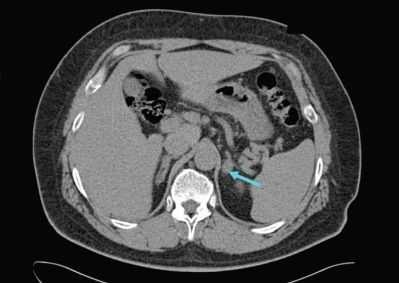

· КТ надпочечников (точность выявления опухолевых образований этим методом достигает 95%). Позволяет определить размеры опухоли, форму, топическое расположение, оценить накопление и вымывание контраста (подтверждает или исключает адренокортикальный рак). Критерии: доброкачественные образования обычно гомогенные, плотность их невысока, контуры четкие;

- Инструментальная визуализация. УЗИ надпочечников и радиоизотопное сканирование (сцинтиграфию) надпочечников используют для выявления имеющихся патологических изменений и уточнения их характера (гиперплазия, опухоль), КТ надпочечников и МРТ надпочечников - для определения локализации и величины альдостеромы.